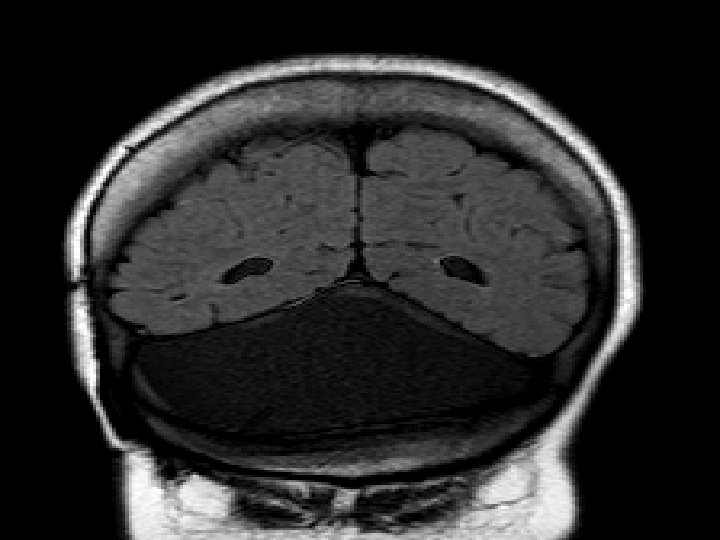

Klassik DW -li xəstə � Cins: qadın � Yaş : 20 � Diaqnoz : Klassik DW � Klinik əlamətlər-əqli inkişafdan geriqalma , hərəkət koordinasiyasının pozulması, yaşıdlarından geriqalma, baş ağrıları � Xəstəyə 04. 08. 2014 tarixində MRT çəkilmişdir

T 1 sagital kəsikdə arxa çuxurda böyük ölçülü kista, hipoplastik soxulcan kist üzərində yuxarıya çevrilib. Beyincik yarımkürələri və beyin kötüyü hipoplastikdir, incəlmiş ənsə pulu

T 2 şəkildə hidrosefaliya, arxa çuxurda böyük BOM kistası incəlmiş ənsə sümüyü və hipoplastik beyincik yarımkürələri qanad şəkilli